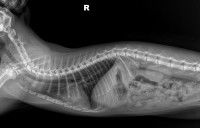

Le squelette du chat comprend en moyenne 230 à 250 os. C'est nettement moins que le nombre d'os du chien, qui en comprend entre 280 et 300. C'est tout de même bien plus que l'être humain, qui n'en compte que 206.

Comme les autres mammifères, le chat est doté d'une colonne vertébrale, qui relie la base de son crâne à sa queue. Elle abrite et protège la moelle épinière, qui correspond au réseau de nerfs chargé de transmettre les messages depuis le cerveau vers le reste du corps, et inversement. Les omoplates, les côtes, les hanches y sont rattachées.

Comme son nom l'indique, la colonne vertébrale est constituée de vertèbres, que l'on peut ranger en plusieurs catégories en fonction de leur localisation :

Cela fait environ 50 vertèbres dans le cas général, et 30 lorsque le petit félin n'a pas de queue.

Quoi qu'il en soit, la colonne vertébrale possède la particularité d'être très souple : c'est ce qui lui permet d'être aussi agile. Grâce à cela, il peut par exemple s'étirer massivement, ou même se retourner sur lui-même.

La queue du chat n'est pas un organe mou : il s'agit en fait du prolongement de la colonne vertébrale chez la plupart des mammifères - contrairement à l'humain, qui lui en est dépourvu.

Ce n'est donc pas surprenant qu'il y ait des os dans la queue du chat. Plus précisément, ce sont des vertèbres, comme dans le reste de la colonne vertébrale : on les appelle les vertèbres caudales. On en compte une vingtaine en moyenne. Bien entendu, plus il y en a, plus l'appendice est long. À l'inverse, un chat à la queue courte n'en contient pratiquement pas.